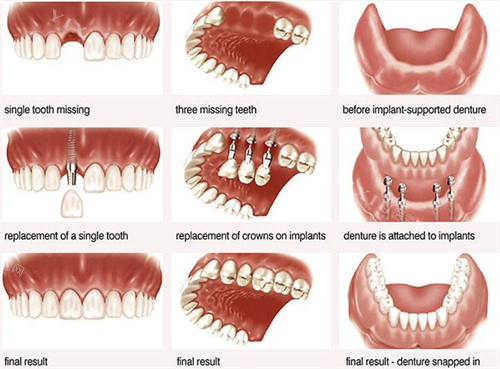

麦绚口腔不仅地理位置优越、营业时间便利,其看牙实力更是不容小觑。院内汇聚了一支经验充足、技术娴熟的口腔医疗团队,医生们均毕业于正规口腔院校,在种植牙、牙齿矫正、牙齿修复等多个领域各有专长。他们定期参加国内外学术交流活动,掌握行业潮流技术,能够针对不同患者的口腔问题,制定个性化的诊疗方案。

同时,麦绚口腔配备了一系列新型的口腔诊疗设备,如智能化口腔 CT 机、3D 口腔扫描仪、智能种植导板系统等。这些设备能够精细获取患者口腔数据,为医生的诊断和治疗提供科学依据,大大提高了诊疗的明确性和效率。无论是复杂的种植牙手术,还是精细的牙齿矫正治疗,都能在这里得到正规、有效的解决。